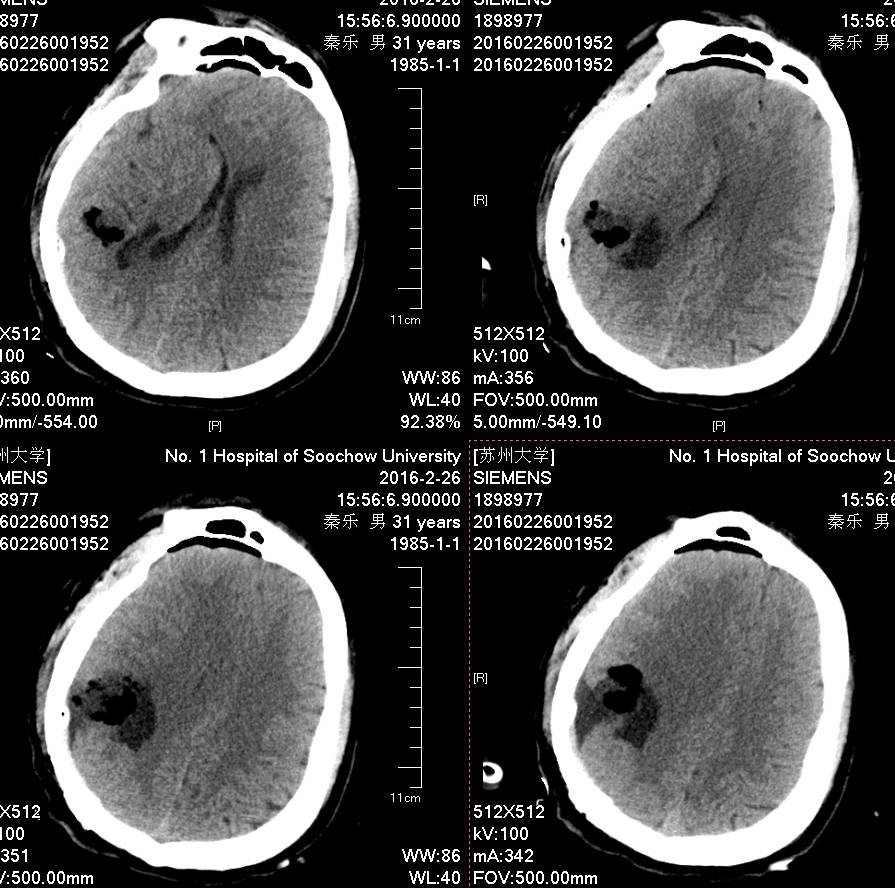

头颅MR示:右颞顶囊性占位伴结节,考虑胶质瘤可能。MRI T1为等信号(图1);T2囊液为高信号(图2);结节为均匀增强(图3);弥散相显示弥散受限(图4)。

术后患者恢复良好,神志清,精神佳,四肢肌力V级,肌张力正常,病理征(-)。术后CT(图5)MRI(图6)未见血肿,肿瘤全切。

图5. 术后2小时CT。

PXA在CT平扫时表现为低密度囊性病变,境界多较清楚;附壁结节呈稍低密度或等密度,壁结节常紧邻软脑膜;囊性区因含有蛋白或出血,在CT上为略高于脑脊液的液性密度。在MRI上T1W1囊性区呈低信号,壁结节为低或等信号,T2W1为囊性区呈高信号,壁结节为稍高信号。增强扫描可见肿瘤附壁结节明显强化,囊壁可轻度强化或不强化,囊壁强化代表囊壁为肿瘤组织,囊壁不强化说明囊壁为反应性增生的胶质细胞构成。影像学典型表现为囊性病变伴壁结节,少数呈囊实性病变,钙化少见。充分认识这些影像特征有助于提高其诊断及鉴别诊断的准确性,为临床治疗及对预后的判断提供重要的参考价值。少数PXA表现不典型,呈囊实性病变,表现为密度或信号不均匀,增强扫描呈不均匀强化。